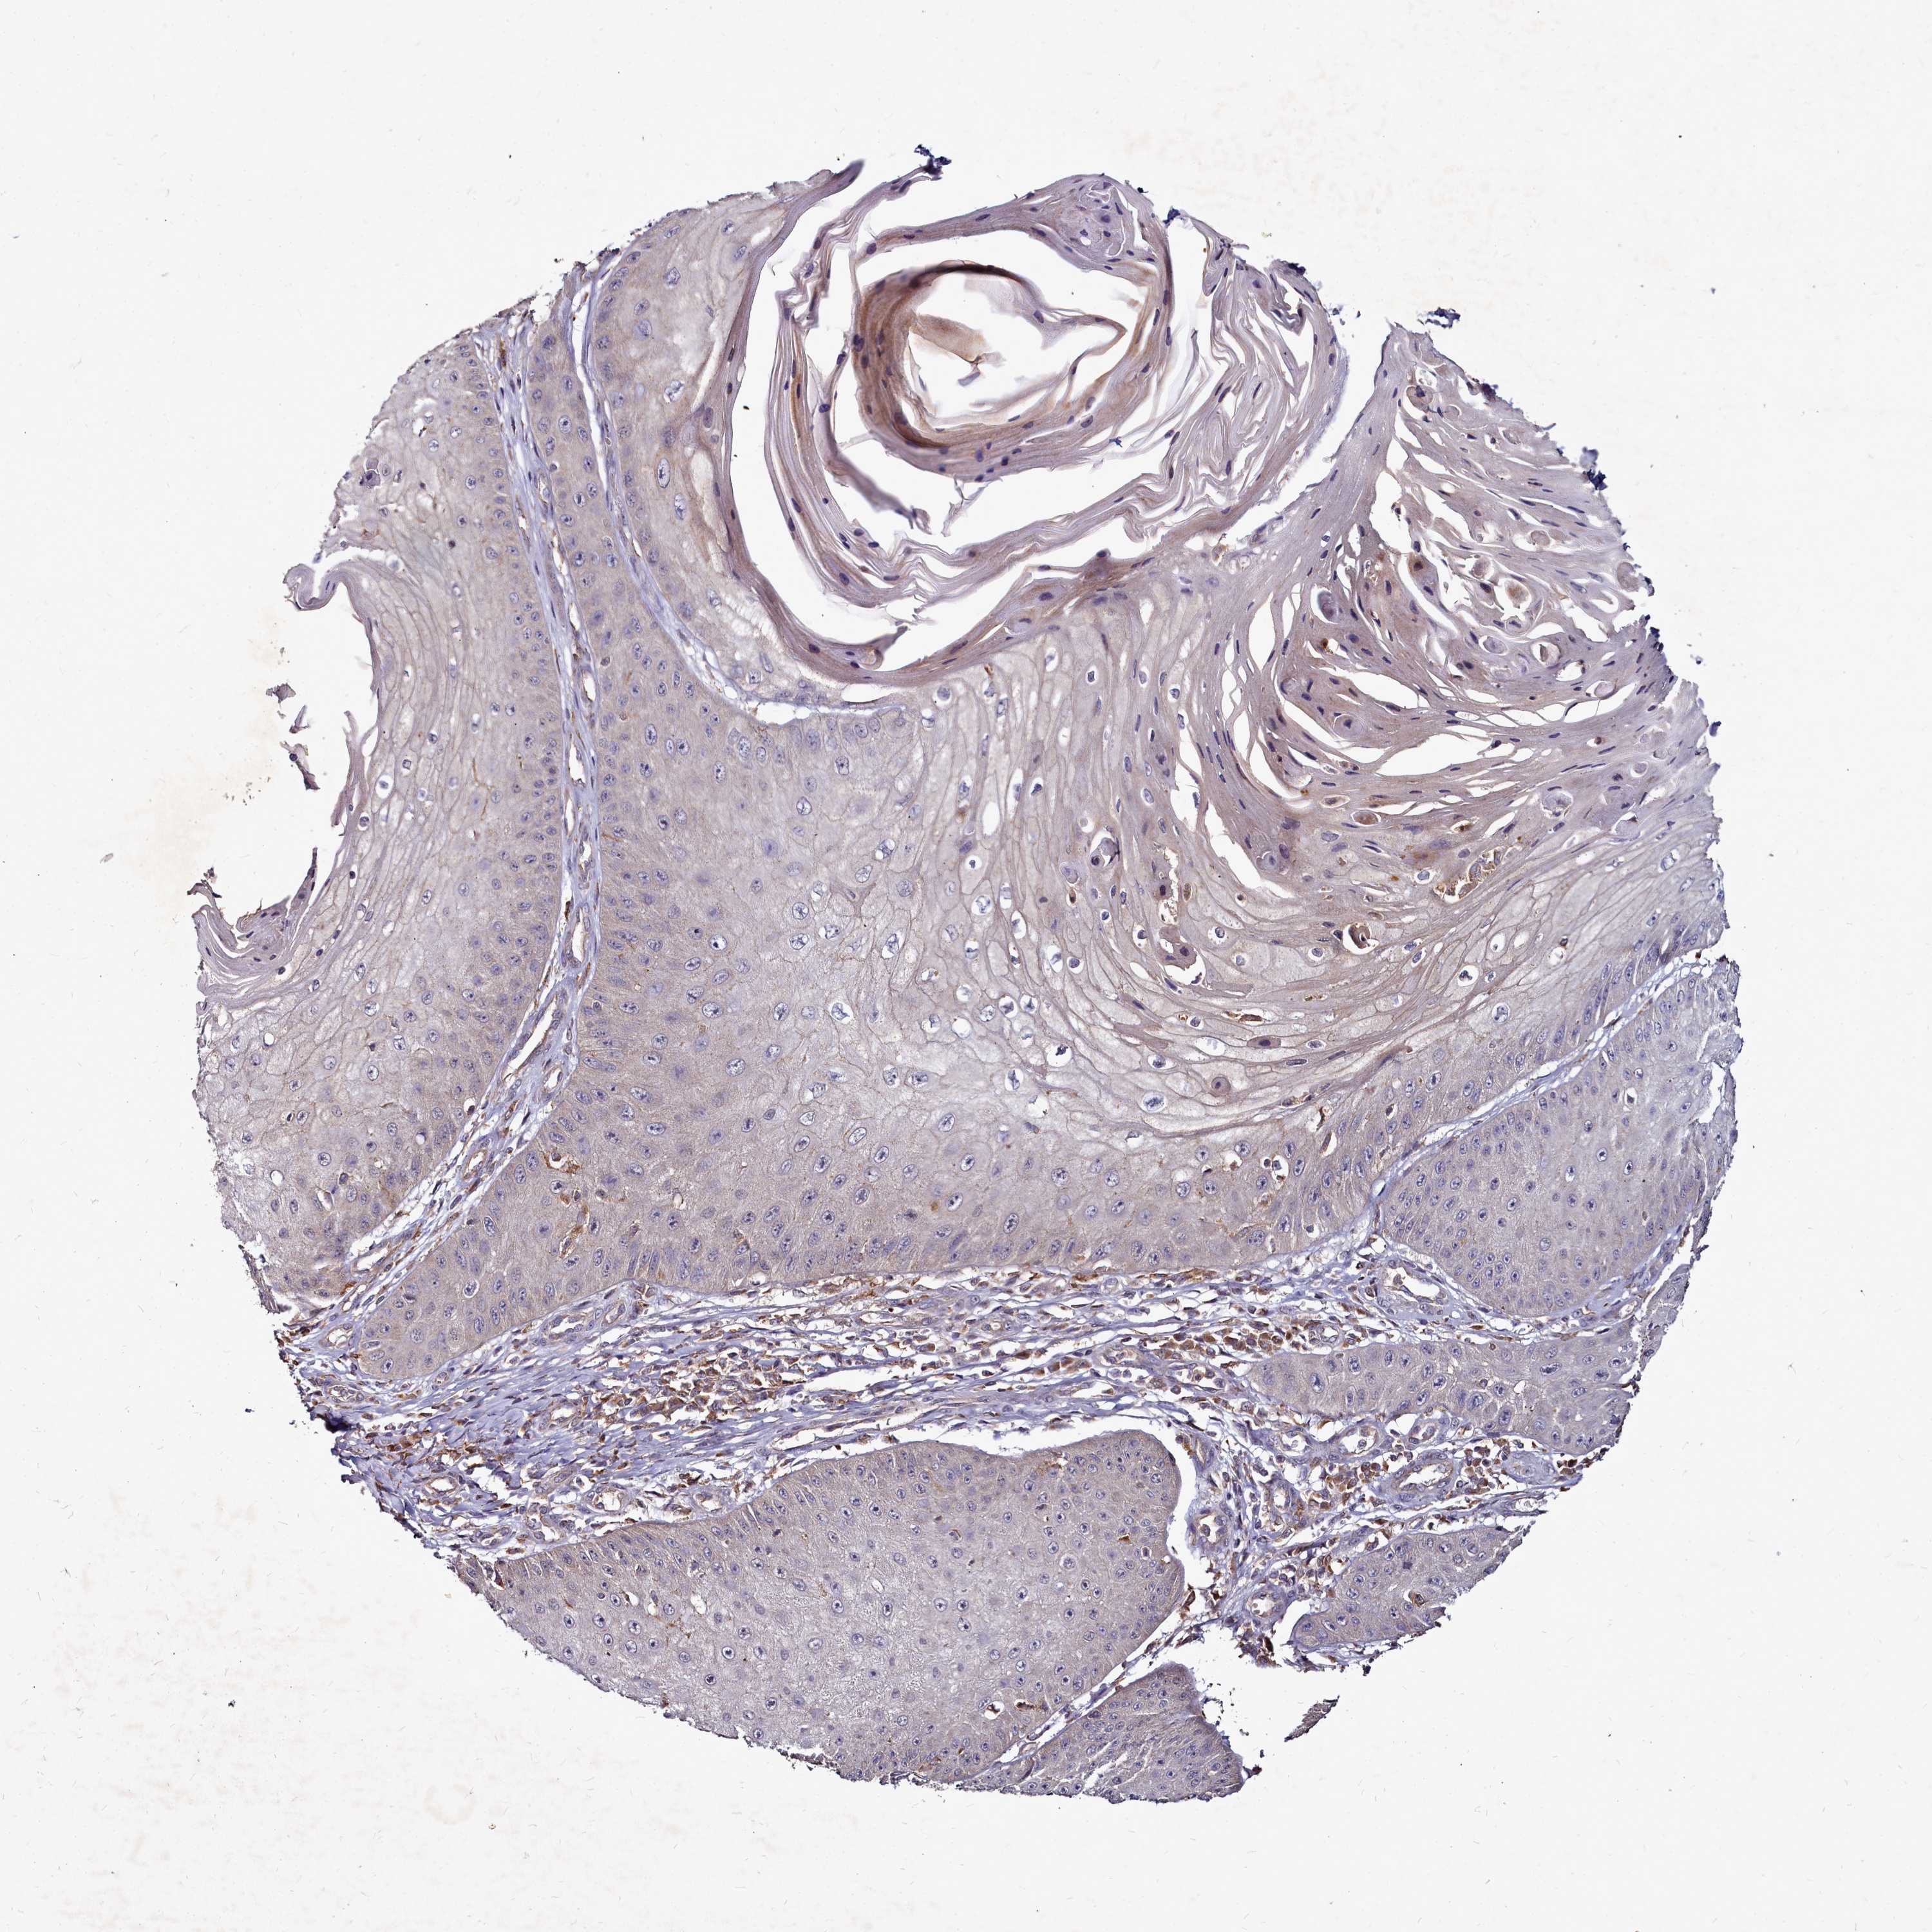

Basal cell and squamous cell cancer

SKIN CANCER - Protein expressioni

A mouse-over function shows sample information and annotation data. Click on an image to view it in a full screen mode. Samples can be filtered based on level of antibody staining by selecting one or several of the following categories: high, medium, low and not detected. The assay and annotation is described here.

Each image is clickable and will lead to virtual microscopy that enables deeper exploration of all samples and also displays staining intensity scores, fraction scores and subcellular localization as well as patient and tissue information for each sample.

Antibody HPA040772

Squamous cell carcinoma, metastatic, NOS